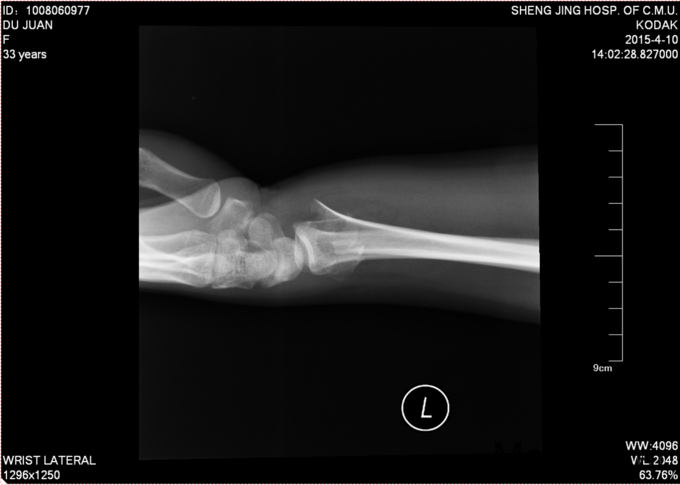

主诉:摔伤后左腕部疼痛活动受限4小时。现病史:4小时前行走时不慎摔倒,手掌着地,导致左腕部疼痛肿胀活动受限,家人急送至我院急诊,行左腕部DR时:桡骨远端骨折。现患者为求进一步诊治要求住院治疗,我科以“科雷斯(colles)骨折”为主要诊断收入我科。患者自受伤以来,无发热,无呼吸困难,饮食睡眠正常,大便未排,小便正常。

患者右手托左腕部步入病房,左腕部肿胀,疼痛(+),压痛(+),骨擦音(+),骨擦感(+),活动受限,皮肤感觉无异常,手指活动灵活,双侧桡动脉可触及。

诊断:科雷斯骨折;治疗:手法复位,石膏固定

术后给予患者止疼消肿等对症治疗,石膏固定后2周后给予复查腕关节正侧位DR,位置良好,更换功能位短石膏。